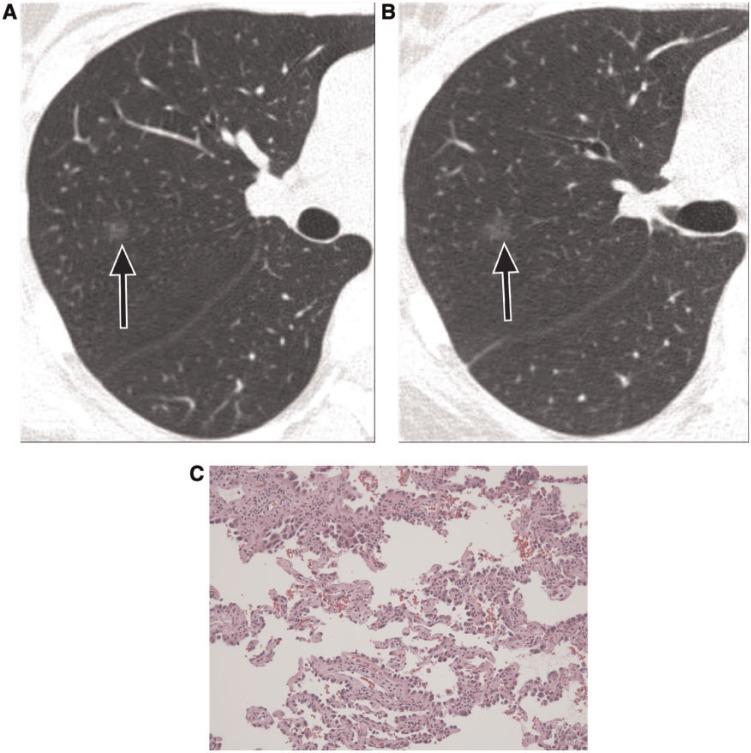

Pulmonary nodules, both solid and subsolid, are common incidental findings on computed tomography (CT) studies. Subsolid nodules (SSNs) may be further classified as either pure ground-glass nodules or part-solid nodules. The differential diagnosis for an SSN is broad, including infection, organizing pneumonia, inflammation, hemorrhage, focal fibrosis, and neoplasm. Adenocarcinomas of the lung are currently the most common type of lung cancer, representing 30-35% of all primary lung tumors, and the subtype of bronchioloalveolar cell carcinoma (BAC) commonly presents as an SSN. In 2011, a new classification system for lung adenocarcinomas was proposed by the International Association for the Study of Lung Cancer, the American Thoracic Society, and the European Respiratory Society. An important feature of the new system is the relinquishment of the term BAC in favor of more specific histologic subtypes. It has been reported that these subtypes are associated with characteristic CT findings. This article reviews the new classification system of lung adenocarcinomas, discusses and illustrates the associated CT findings, and outlines the current recommendations for further diagnosis, treatment, and follow-up of SSNs based on computed tomography findings.

肺部结节,无论是实性还是亚实性,都是计算机断层扫描(CT)研究中的常见偶然发现。亚实性结节(SSN)可进一步分为纯磨玻璃结节或部分实性结节。SSN 的鉴别诊断范围很广,包括感染、机化性肺炎、炎症、出血、局灶性纤维化和肿瘤。肺腺癌是目前最常见的肺癌类型,占所有原发性肺肿瘤的 30-35%,而细支气管肺泡细胞癌(BAC)亚型通常表现为 SSN。2011 年,国际肺癌研究协会、美国胸科学会和欧洲呼吸学会提出了一种新的肺腺癌分类系统。该系统的一个重要特点是放弃 BAC 一词,转而采用更具特异性的组织学亚型。据报道,这些亚型与特征性 CT 表现有关。本文回顾了肺腺癌的新分类系统,讨论并说明了相关的 CT 发现,并概述了基于 CT 发现对 SSN 进行进一步诊断、治疗和随访的当前建议。